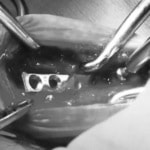

脊髄の減圧、脊柱管の再構築・安定化を目的に、片側椎弓切除術およびMatrixMANDIBLE Plateによる椎体固定を実施しました。

隣接椎体を架橋するようにプレートを設置しました。

Arthrex社のターゲティングデバイスを用いてピンニングの位置を調整することで、確実な固定を行っています。当院ではこの手術器具以外にも、人の手術にも使用される様々な器具を導入し、手術精度を高め、また医療メーカーと新しい器具の開発、試作にも取り組んでおります。